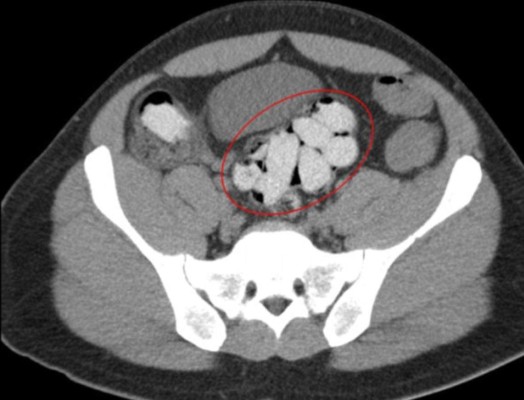

Las ocho pacientes ingresaron al hospital de San Cristóbal el jueves por la noche y 'traían dentro de su cuerpo dediles', confirmó a la AFP el subdirector de ese centro de salud, Edgar Suárez.